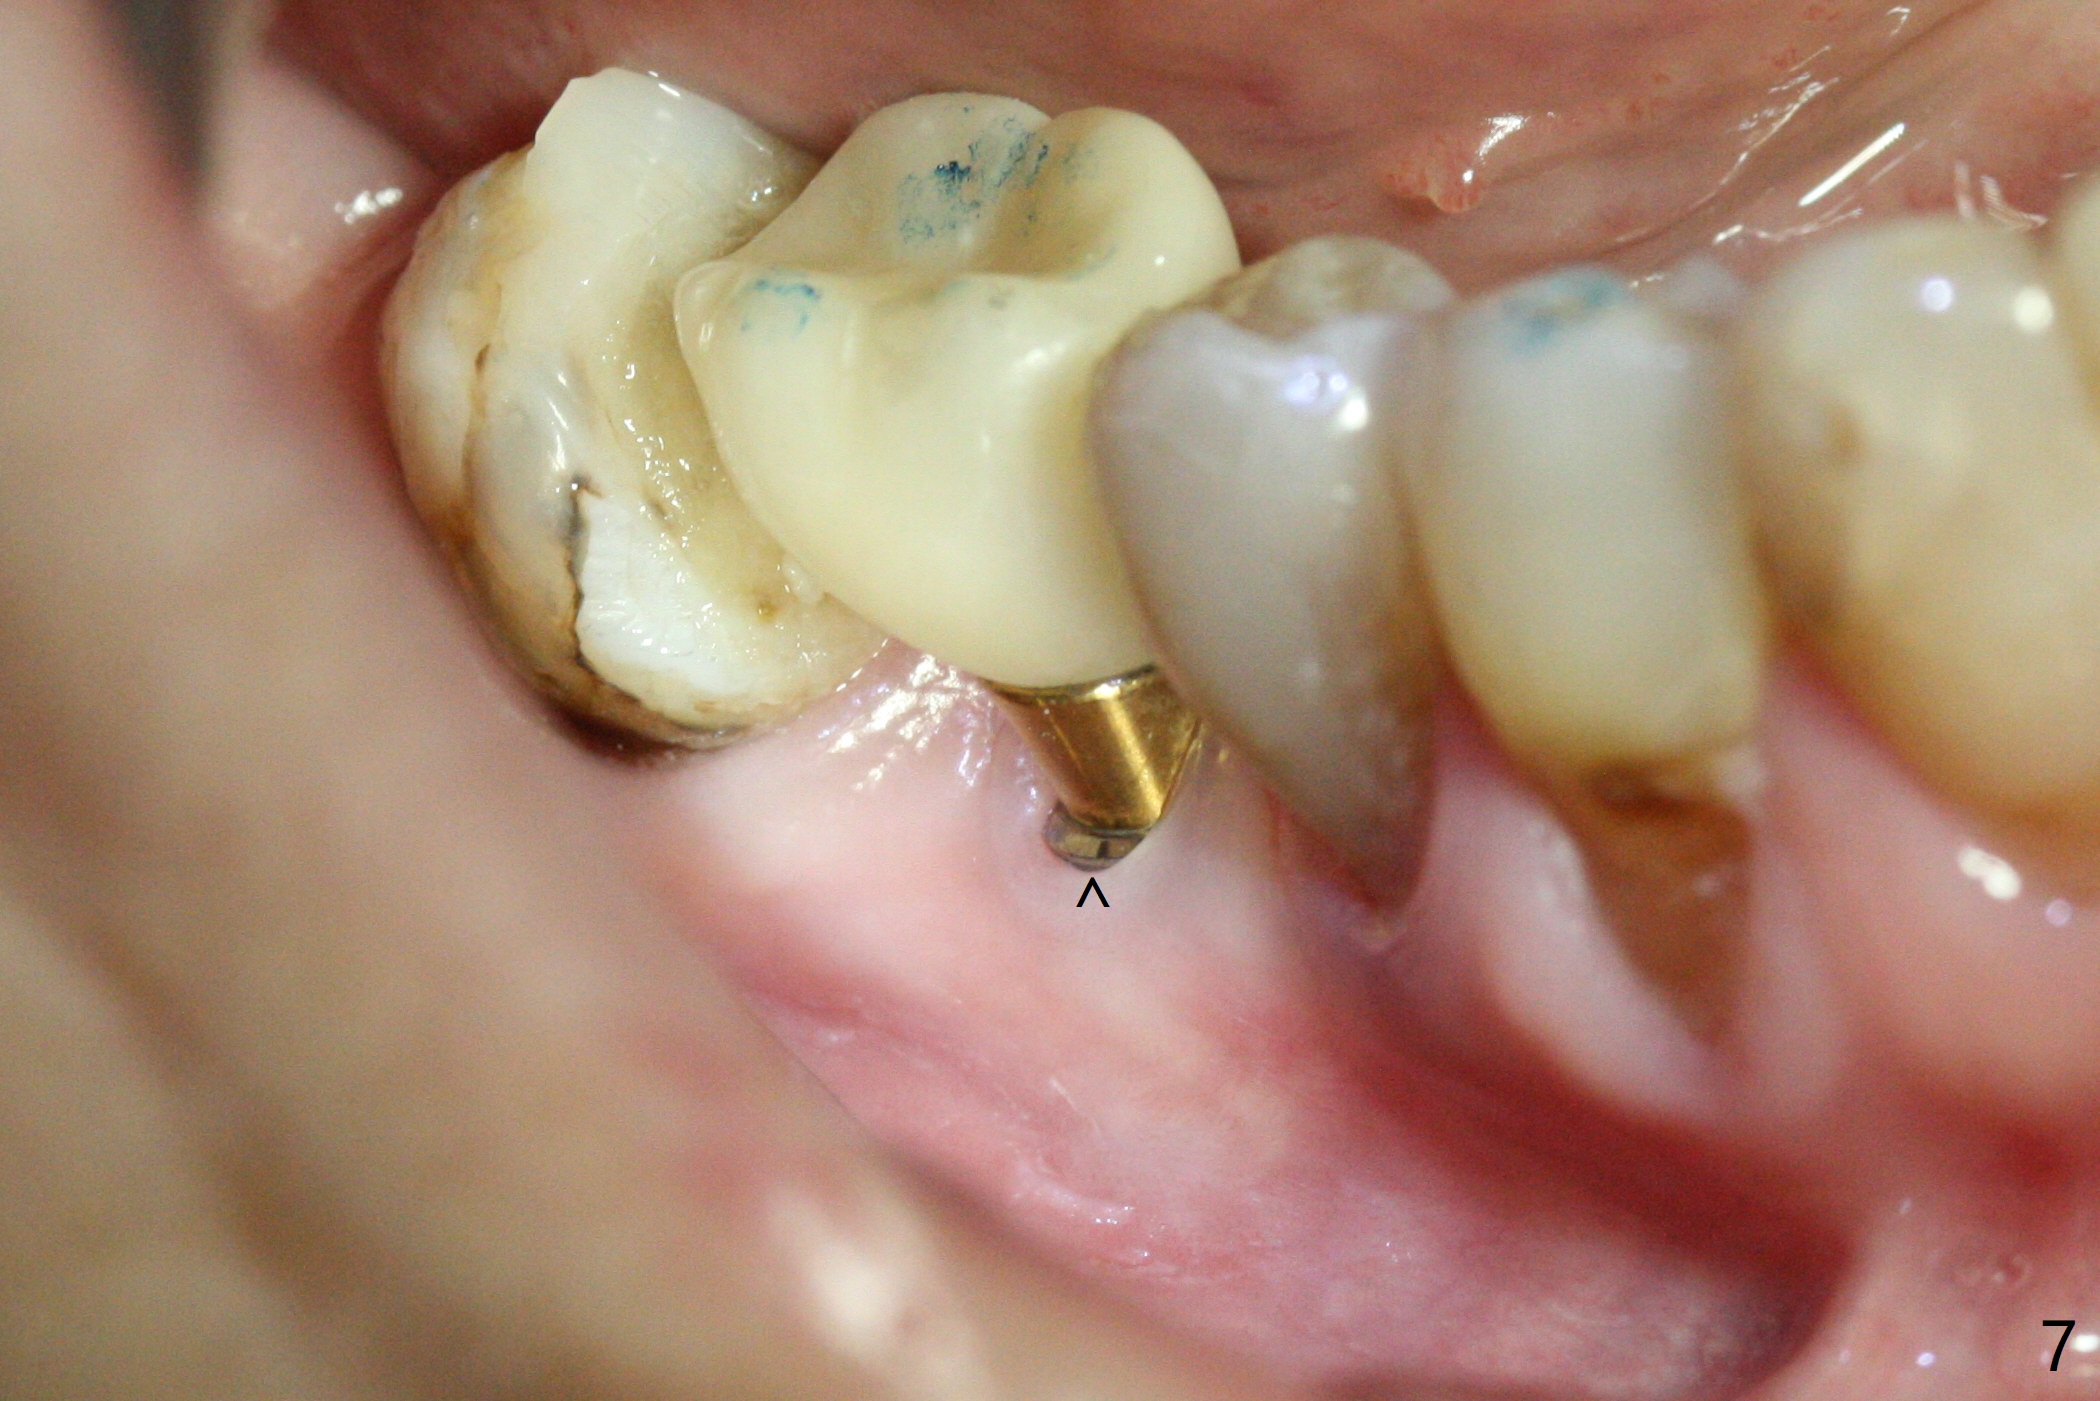

When the patient returns for #29 composite a month later, there is buccal implant exposure at #30 (Fig.7 ^, 2 years 9 months post cementation). It appears that the implant (4.5x12 mm) may have been placed shallow and buccal or may have been too large for the site.